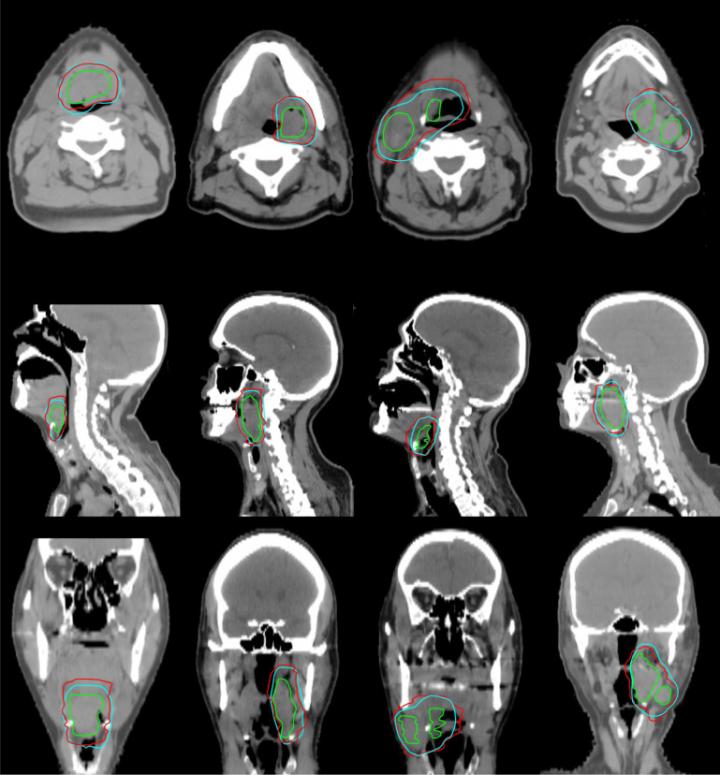

Before performing radiation therapy, radiation oncologists first carefully review medical images of a patient to identify the gross tumor volume -- the observable portion of the disease. They then design patient-specific clinical target volumes that include surrounding tissues, since these regions can hide cancerous cells and provide pathways for metastasis.

Known as contouring, this process establishes how much radiation a patient will receive and how it will be delivered. In the case of head and neck cancer, this is a particularly sensitive task due to the presence of vulnerable tissues in the vicinity.

Though it may sound straightforward, contouring clinical target volumes is quite subjective. A recent study from Utrecht University found wide variability in how trained physicians contoured the same patient's computed tomography (CT) scan, leading some doctors to suggest high-risk clinical target volumes eight times larger than their colleagues.

The model uses the gross tumor volume and distance map information from surrounding anatomic structures as its inputs. It then classifies the data to identify voxels -- three-dimensional pixels -- that are part of the high-risk clinical target volumes. In oropharyngeal cancer cases, the head and neck are usually treated with different volumes for high, low and intermediate risk. The paper described automating the target for the high-risk areas. Additional forthcoming papers will describe the low and intermediate predictions.

Cardenas and his collaborators tested the method on a subset of cases that had been left out of the training data. They found that their results were comparable to the work of trained oncologists. The predicted contours agreed closely with the ground-truth and could be implemented clinically, with only minor or no changes.